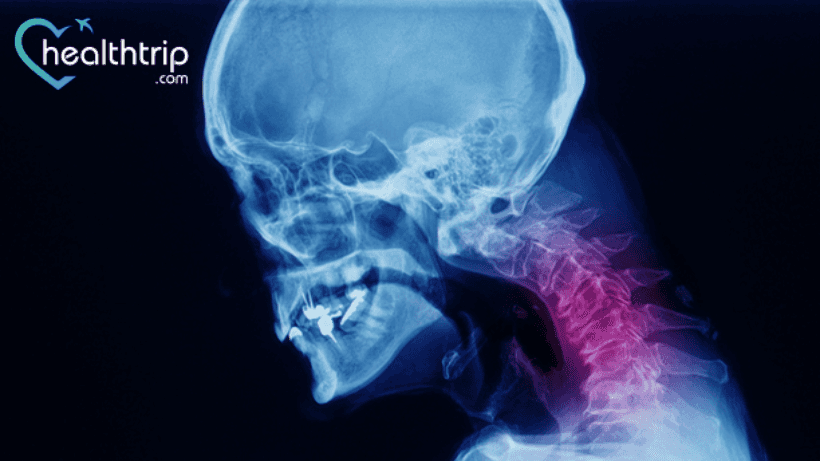

Setiap yang lainpembedahan atau prosedur membawa beberapa risiko dan komplikasi. Tetapi, walaupun risiko rendah untuk beberapa pembedahan, anda tidak boleh mengabaikan peluang untuk membangunkan komplikasi yang serius. Di sini kami telah membincangkan komplikasi pembedahan serviks anterior dan pembedahan fusion. Teruskan membaca untuk mempelajari perkara yang sama.

Diskektomi dan gabungan serviks anterior biasanya disyorkan untuk pesakit yang mengalami spondylosis serviks atau herniasi cakera dengan mielopati/radikulopati yang

tidak bertindak balas terhadap terapi konservatif. Selain itu, ia mungkin ditunjukkan dalam proses malignan, trauma, atau berjangkit tertentu pada vertebra serviks yang menyebabkan ketidakstabilan.

Prosedur ini dilakukan melalui hirisan leher anterolateral, dengan pendekatan pembedahan melepasi medial antara saluran aerodigestive (trakea, esofagus, otot pharyngeal) dan secara lateral antara berkas neurovaskular karotid (arteri karotid, urat jugular dalaman, saraf vagus).

Cakera intervertebral dan fibrocartilage yang meliputi plat hujung vertebra bersebelahan kemudian dikeluarkan (untuk membolehkan gabungan tulang akhirnya). Mencapai kembali ke ligamen longitudinal posterior, mengeluarkan osteofit dan tonjolan cakera serta memanjang ke sisi untuk menyahmampat foramina keluar saraf, adalah mungkin.

Selepas penyahmampatan, beberapa jenis pengatur jarak antara badan diperkenalkan untuk membantu gabungan/meningkatkan kestabilan.

Selepas itu, plat serviks anterior dengan skru yang masuk ke dalam badan vertebra di atas dan di bawah segmen pembedahan biasanya digunakan untuk memberikan kestabilan tambahan..

- Radiografi serviks sisi adalah cara biasa untuk menilai pembengkakan tisu lembut prevertebral selepas pembedahan sedemikian.